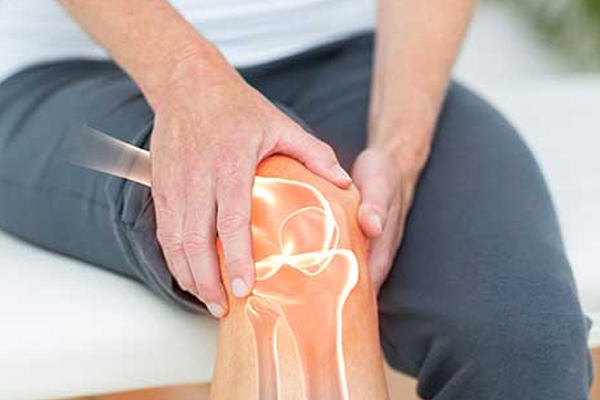

Knee Pain

Knee Treatments